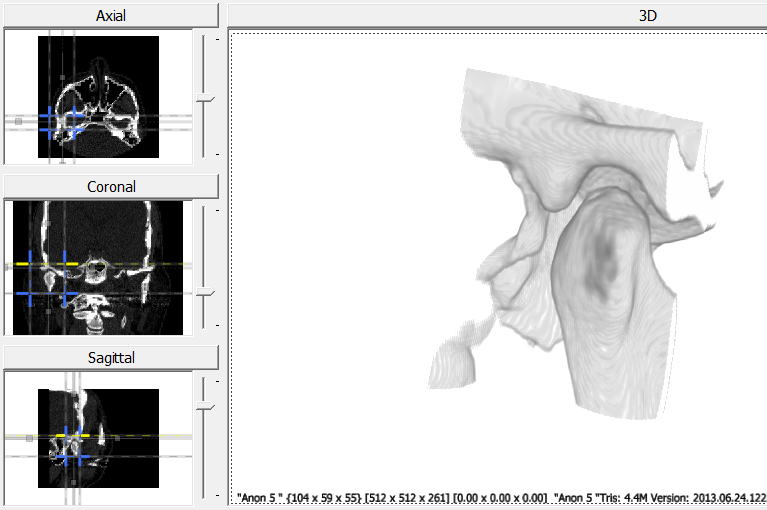

The following explains how to use a joint primitive to setup specimens for populations used in joint congruence using Stratovan Checkpoint. The example creates condyle and fossa specimens of the temporomandibular joint (TMJ) for their respective populations from a joint primitive. This tutorial includes:

- Loading a CT scan and using cropping to isolate a region of interest around the TMJ.

Load Scan and Export Volume

- Load a CT scan of a head. For this example, the scan includes both the fossa and condyle.

- Use the cropping lines to isolate the region of interest.

- In the export tab, click on “Export Volume” to save the cropped volume. To export the reflected volume, click on “Export Reflected Volume”.